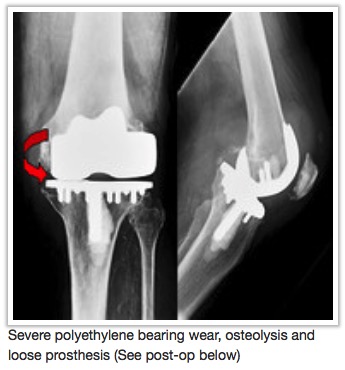

Does your knee replacement need replacing?

As people live longer and more people receive knee replacements at younger ages, it is expected that an increasing number of those implants will wear out and/or fail for some reason. In these cases, a second operation will be necessary to replace or revise the failed first replacement and this procedure is referred to as revision knee replacement. The increasing demands placed on these implants by patients in terms of longevity and durability; and expectations of patients to maintain their active lifestyles even with a knee replacement has presented a considerable reconstructive challenge to the surgeon.

In almost all cases the presenting symptom of failure of a knee implant is PAIN! This is especially true if the implant is coming loose or there is an infection around the implant. Associated symptoms include

stiffness of the joint or a persistent limp caused by the failing joint.

Each of these symptoms should be evaluated to help determine if the knee replacement has something wrong with it or is functioning as expected. A variety of tests are available and often many of them are necessary to sort out the issues that have

left the primary knee replacement dysfunctional. Many of the common causes for failed total knee which would lead to the need for a revision of part or all of the implant are discussed on our website.